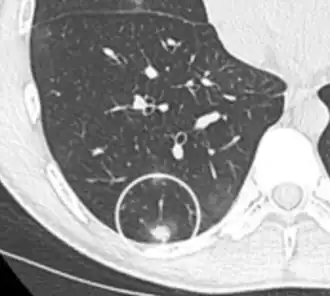

FDG-PET study of a 71-year-old woman with a solitary pulmonary nodule (thin arrow) in the left lower lobe near the heart. The scan also revealed abnormal increased activity at the gastro-esophageal junction (thick arrow). The final diagnosis was non-Hodgkin lymphoma at both sites.

If there is an intermediate risk of malignancy, further imaging with positron emission tomography (PET scan) is appropriate (if available). It can be done simultaneously as a CT scan in the form of PET-CT. Around 95% of patients with a malignant nodule will have an abnormal PET scan, while around 78% of patients with a benign nodule will look normal on PET (this is the test sensitivity and specificity).[15] Thus, an abnormal PET scan will reliably pick up cancer, but several other types of nodules (inflammatory or infectious, for example) will also show up on a PET scan. If the nodule has a diameter of less than one centimeter, PET scans are often avoided because of an increased risk of falsely normal results.[15][16][17] Cancerous lesions usually have a high metabolism on PET, as demonstrated by their high uptake of FDG (a radioactive sugar).